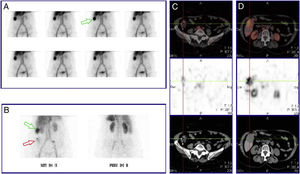

Mujer de 75 años, en estudio por un cuadro de anemia microcítica-hipocrómica de 3 años de evolución, tratada en varias ocasiones con hierro oral y transfusiones sanguíneas. Presentaba afección hemorroidal y deposiciones oscuras en relación con la terapia férrica. El último control analítico reveló Hb 10g/dl, VCM 72f/l, hierro 47μg/dl, ferritina 250ng/ml, vitamina B12 378pg/ml y ácido fólico 6ng/ml. En la endoscopia digestiva alta se objetivó gastritis eritematosa leve con gran hernia de hiato por deslizamiento, mientras que la colonoscopia mostró hemorroides internas y colón espástico, sin signos de sangrado activo en ambas pruebas. Ante la sospecha de sangrado oculto se realizó gammagrafía con hematíes marcados con 99mTc-pirofosfato de estaño (figs. 1A y B) y SPECT/TC abdominal (figs. 1C y D), revelando captación endoluminal del trazador en extremo distal del colon ascendente compatible con hemorragia de bajo débito. Adicionalmente, se identificó un área hipercaptante redondeado y bien delimitado en segmento V hepático correspondiente a hemangioma. En la TC abdominal con contraste iv (fig. 2) se objetivó el patrón típico de captación progresiva centrípeta que apoyaba el diagnóstico de hemangioma hepático, sin evidencia de alteraciones en asas intestinales. Fue tratada con 100mg hierro-trivalente/2 semanas y se repitió estudio esófago-gastro-duodenal, tránsito intestinal con bario y colonoscopia, sin detectarse alteraciones significativas. Actualmente la paciente se encuentra asintomática, mostrando en los controles analíticos valores de Hb estables.

Gammagrafía con hematíes marcados con 99mTc-pirofosfato de estaño, imágenes dinámicas durante una hora: distribución fisiológica del trazador, sin evidencia de focos hemorrágicos. Área hipercaptante de morfología nodular en hipocondrio derecho (flecha verde) (A). Imágenes tardías a las 24h postinyección: persiste área de hipercaptación a nivel del hipocondrio derecho (flecha verde). Captación de nueva aparición, baja intensidad y carácter difuso en fosa ilíaca derecha (flecha roja) (B). Modalidad SPECT/CT abdominal a las 24h postinyección: captación endoluminal del trazador en extremo distal del colon ascendente, que aumenta su actividad en el tiempo, compatible con hemorragia de bajo débito (C). Imagen nodular hipercaptante en segmento V hepático indicativo de estructura vascular fija (hemangioma) (D).